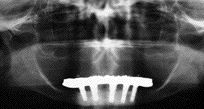

The Implant Retained Overdenture and Its Cost-Effectiveness

FIGURE 5B

The mandibular 2-implant overdenture to is the first-choice standard of care for edentulous patients today.1 Combined with a maxillary conventional denture, it will provide better function and quality of life than conventional dentures.2 Only a small percentage of implant candidates have received treatment.3 Even though decay rates are dropping, in real numbers, people with one … Read more